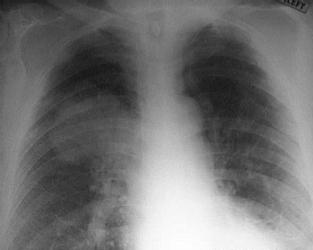

枸橼酸杆菌肺炎是由枸橼酸杆菌感染所致。枸橼酸杆菌为肠杆菌科枸橼酸杆菌属,它包括3种,即异型枸橼酸杆菌、弗劳地枸橼酸杆菌和无丙二酸枸橼酸杆菌。是医院常见的获得性感染,临床表现与一般急性细菌性肺炎相似。主要症状为畏寒、发热、咳嗽、咳黄痰或白黏痰、胸痛,呼吸困难。部分病人可有腹痛、腹泻等消化道症状。且该菌对多种抗生素耐药,治疗较困难,预后差。